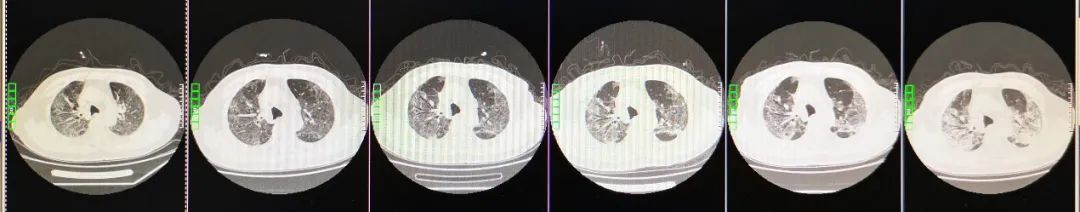

病程中患者胸部CT变化:

(从左至右)3-13,3-5,3-1,2-23,2-18,2-12

患者于2月12日行胸部CT,影像学表现为两肺感染性病变,考虑病毒性肺炎。两肺见弥漫分布磨玻璃影,纵膈窗显示两肺门无增大,气管支气管通畅,纵膈未见肿大淋巴结,心脏、大血管未见异常。我们还注意到病人肺部CT的前后变化对比:2020年2月18日:两肺病灶较前相仿。2020年2月23日:两肺病灶较前相仿。2020年3月1日:较前稍吸收。2020年3月5日:两肺病灶较前部分吸收好转。2020年3月13日:较前进一步吸收好转。